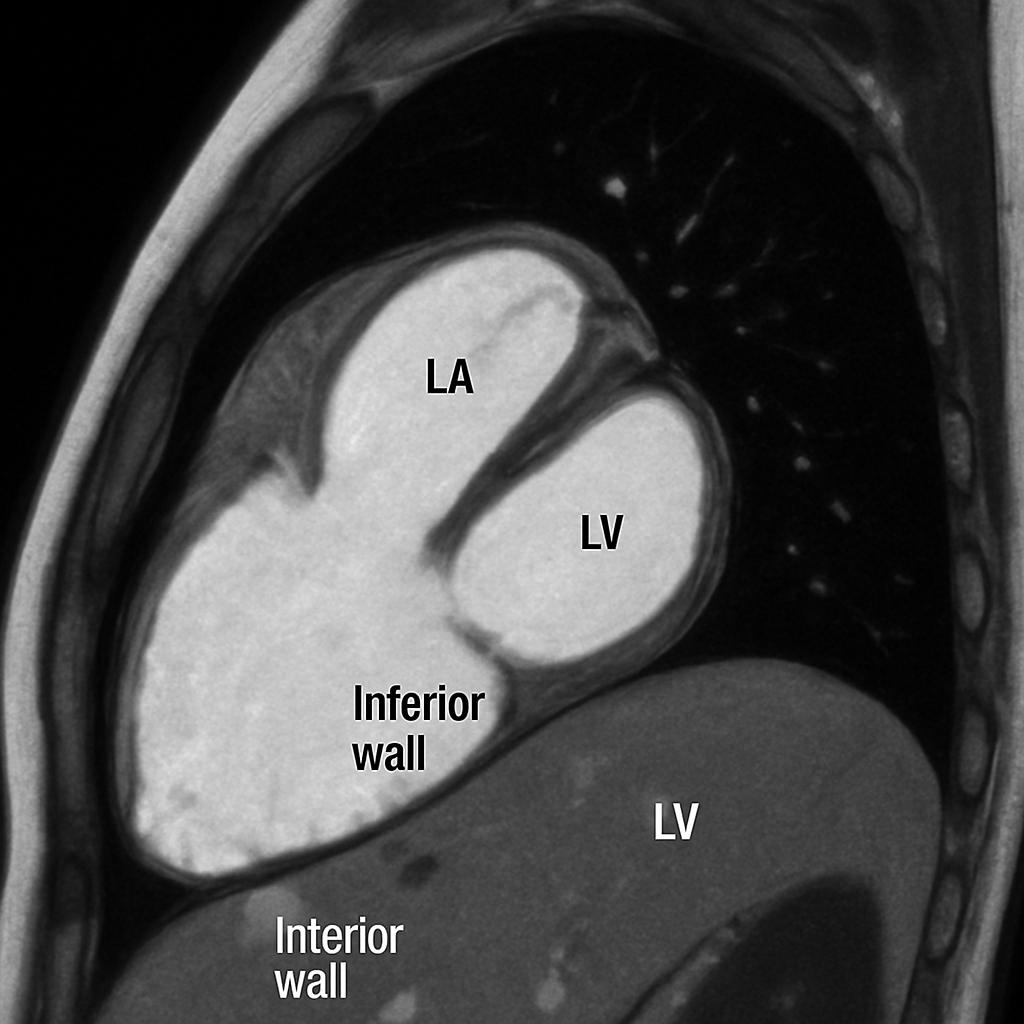

MRI — Two-Chamber View

Cardiac MRI two-chamber (2CH) long-axis view showing left atrium, mitral valve, and left ventricle with anterior and inferior walls. SSFP bright-blood.

MRI AI Generated 2026-03-16

Ssfp Two Chamber

bSSFP cine, two-chamber view (vertical long axis). Show LA, MV, LV anterior and inferior walls.